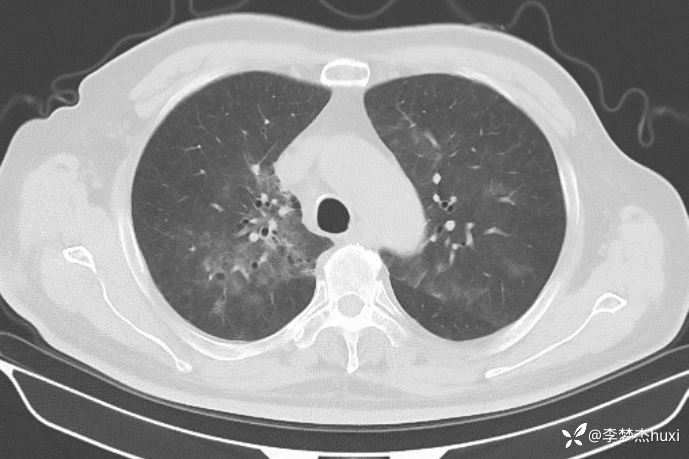

男性74岁,莫西沙星治疗加重的肺炎,可能什么病原菌?

既往史:既往高血压病史 20 余年,最高 180/90mmHg,平素口服降压零号治疗,控制可;糖尿病病史 20 余年,平素应用诺和灵 30R,控制良好;右肺鳞癌病史11月,放疗结束3天,期间放射性食管炎,目前仍吞咽痛;否认冠心病病史;否认“肝炎”、“结核”等传染病史;否认外伤史,否认手术史,无输血史,否认药物、食物过敏史;预防接种史不详,系统回顾无特殊。。

临床诊断:感染性发热。

治疗经过:莫西沙星、喜炎平治疗进展

讨论:可能什么病原体?